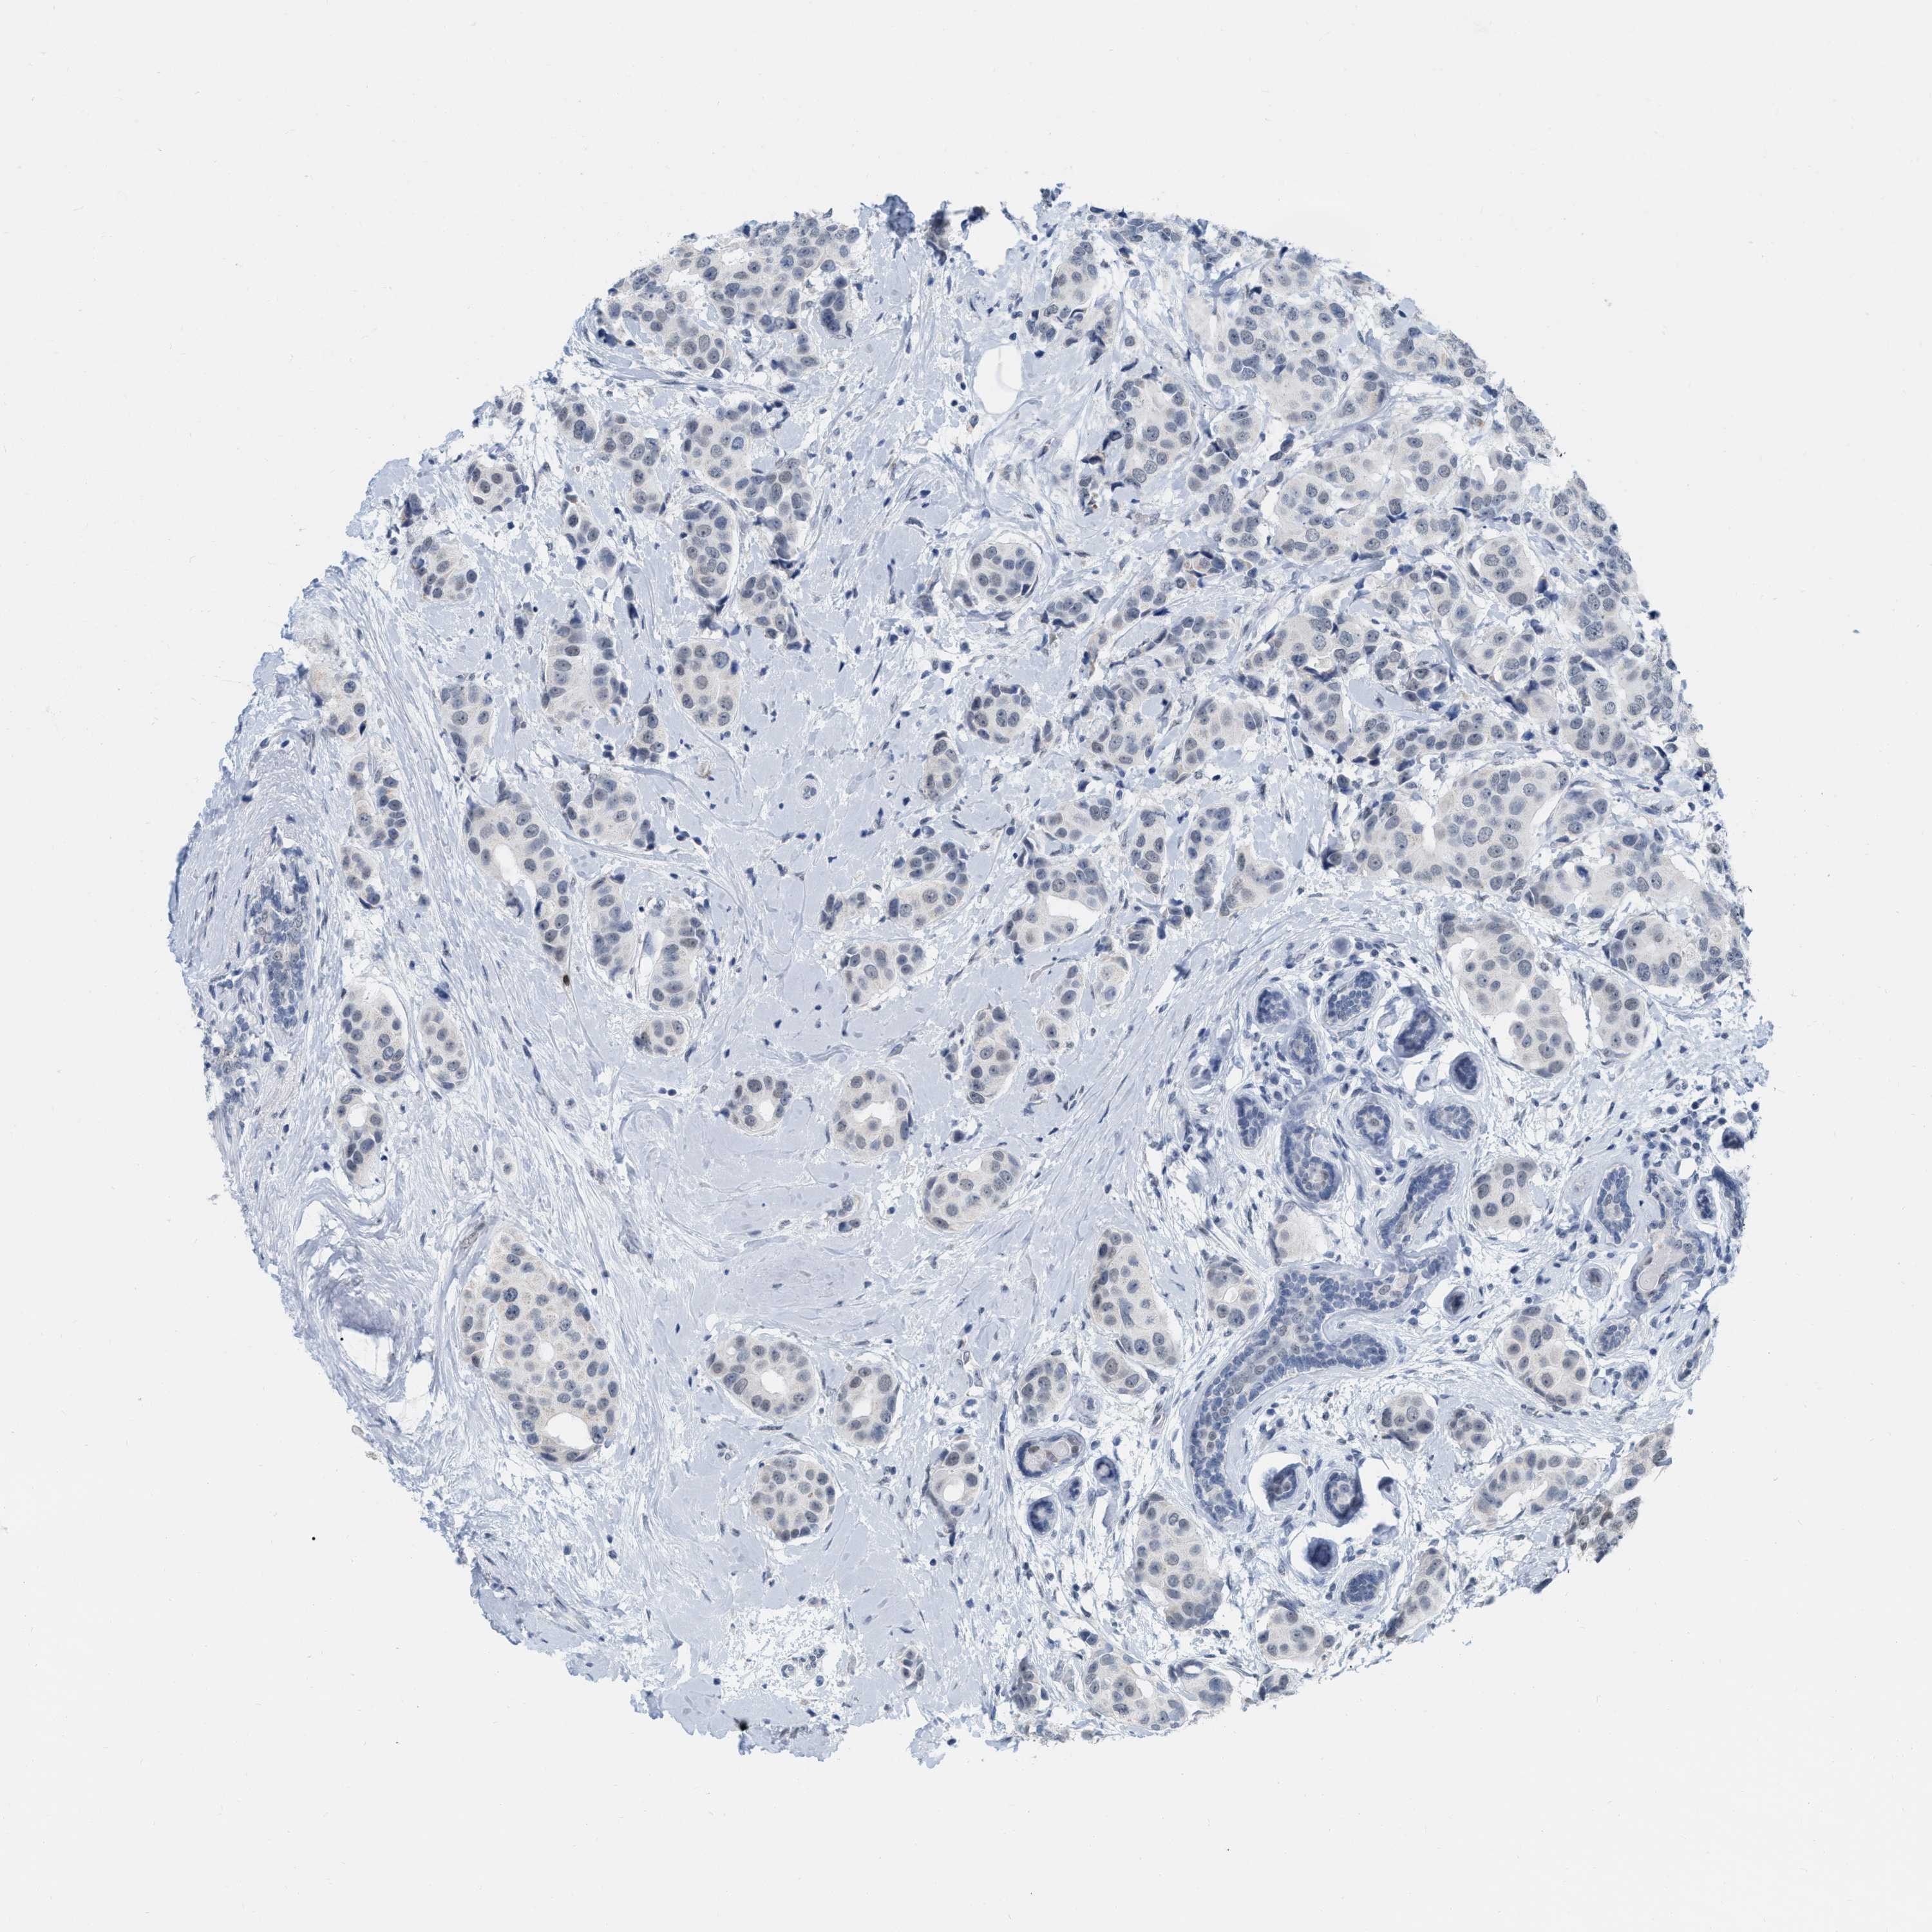

BRCA TCGA BRCA VALIDATION PROTEIN EXPRESSION